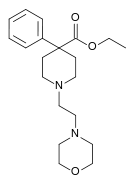

4-Phenylpiperidines

Pethidines (meperidines)

- Piminodine

Structures